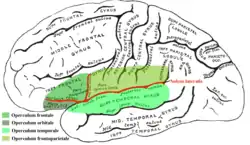

| Operculum (brain) | |

FCMS is primarily originates from damages in the posterior region of the inferior frontal gyrus and inferior region of the precentral gyrus.[6] Anatomically, the word operculum is defined as the cortices encompassing the insula, which includes the pre and post-central, inferior-frontal, supramarginal, angular inferior parietal, and superior temporal convolutions.[1] Parts of the brain such as Heschl's gyrus, Brodmann's area, Broca's area, Wernicke's area are amongst the most relevant in the operculum. These areas are responsible for auditory functions for language and speech.[7]

The opercular cortex surrounding the insula is separated by two anatomical components: the ascending rami of the lateral sulcus and the posterior rami into three different sections of the operculum.[3]

- Frontal operculum formed by posterior part of the inferior frontal gyrus.

- Fronto-parietal opercula formed by the lowermost part of the precentral and postcentral gyrus and the anterior and lowermost part of the inferior parietal lobule.

- Temporal opercula formed by the superior temporal gyrus.[3]